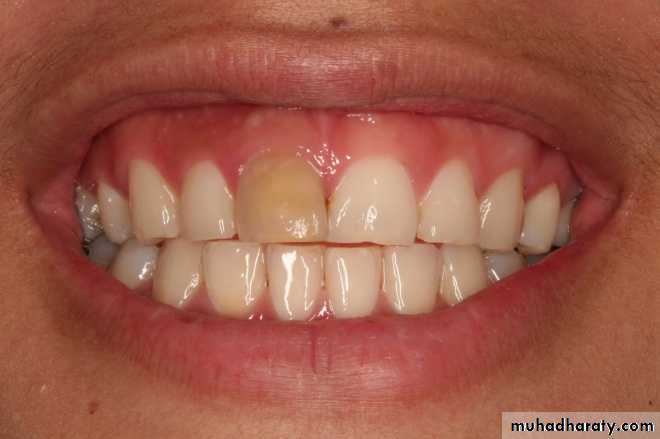

b. Hyperplastic form (pulp polyp) is overgrowth of granulomatous tissue into carious cavity.

• Hyperplastic form of chronic pulpitis is seen in teeth of children and adolescents in which pulp tissue has high resistance and large carious lesion permit free proliferation of hyperplastic tissue. Since it contains few nerve fibers, it is non-painful but bleeds easily due to rich network of blood vessels.

• Pain:It is usually absent.• Hyperplastic form shows a fleshy, reddish pulpal mass which fills most of pulp chamber or cavity. It is less sensitive than normal pulp but bleeds easily when probed.